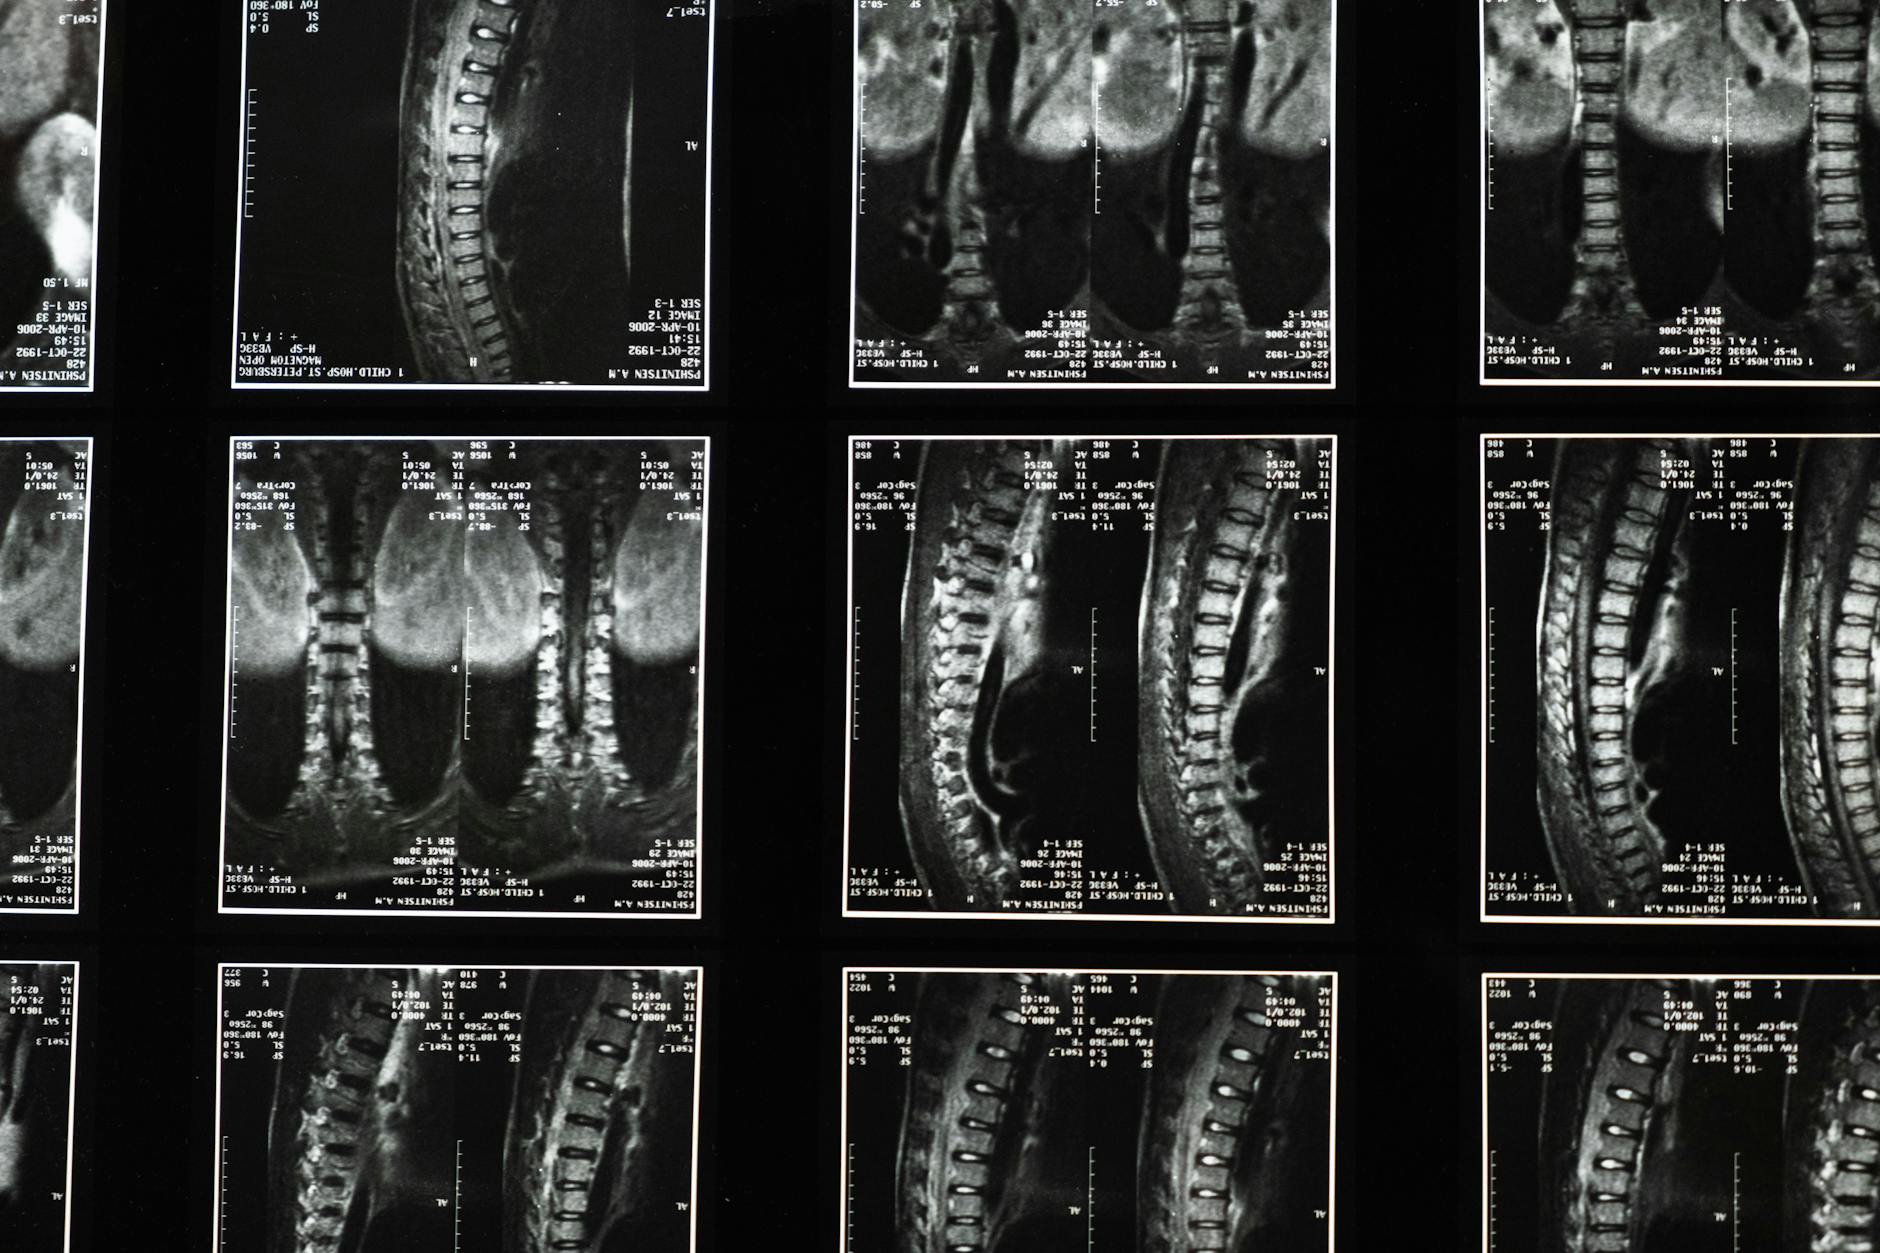

Neuropathic Pain Severity Is Associated With Opioid Use in Adults With Traumatic Spinal Cord Injury: A Spinal Cord Injury Model System Study.

This study provides critical insight into opioid use patterns among adults with spinal cord injury experiencing neuropathic pain, a population with limited effective treatment options. Understanding these associations helps clinicians identify patients at higher risk for opioid dependence and optimize multimodal pain management strategies.

This cross-sectional study analyzed 283 adults with spinal cord injury across 6 SCI Model System centers, examining factors associated with opioid use for neuropathic pain. Of the participants, 104 were current opioid users and 179 were non-users. Employment status emerged as protective, with employed individuals showing 33% lower odds of opioid use compared to unemployed participants. Opioid users were more likely to use anti-epileptic medications and combination therapies including cannabis with anti-epileptics, suggesting these patients had more severe, treatment-resistant neuropathic pain requiring multimodal approaches.